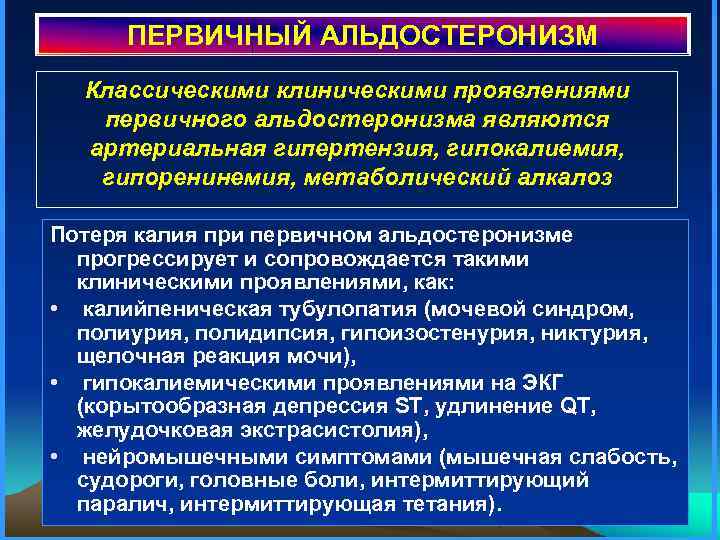

ПЕРВИЧНЫЙ АЛЬДОСТЕРОНИЗМ Классическими клиническими проявлениями первичного альдостеронизма являются артериальная гипертензия, гипокалиемия, гипоренинемия, метаболический алкалоз Потеря калия при первичном альдостеронизме прогрессирует и сопровождается такими клиническими проявлениями, как: • калийпеническая тубулопатия (мочевой синдром, полиурия, полидипсия, гипоизостенурия, никтурия, щелочная реакция мочи), • гипокалиемическими проявлениями на ЭКГ (корытообразная депрессия ST, удлинение QT, желудочковая экстрасистолия), • нейромышечными симптомами (мышечная слабость, судороги, головные боли, интермиттирующий паралич, интермиттирующая тетания).

ПЕРВИЧНЫЙ АЛЬДОСТЕРОНИЗМ Классическими клиническими проявлениями первичного альдостеронизма являются артериальная гипертензия, гипокалиемия, гипоренинемия, метаболический алкалоз Потеря калия при первичном альдостеронизме прогрессирует и сопровождается такими клиническими проявлениями, как: • калийпеническая тубулопатия (мочевой синдром, полиурия, полидипсия, гипоизостенурия, никтурия, щелочная реакция мочи), • гипокалиемическими проявлениями на ЭКГ (корытообразная депрессия ST, удлинение QT, желудочковая экстрасистолия), • нейромышечными симптомами (мышечная слабость, судороги, головные боли, интермиттирующий паралич, интермиттирующая тетания).